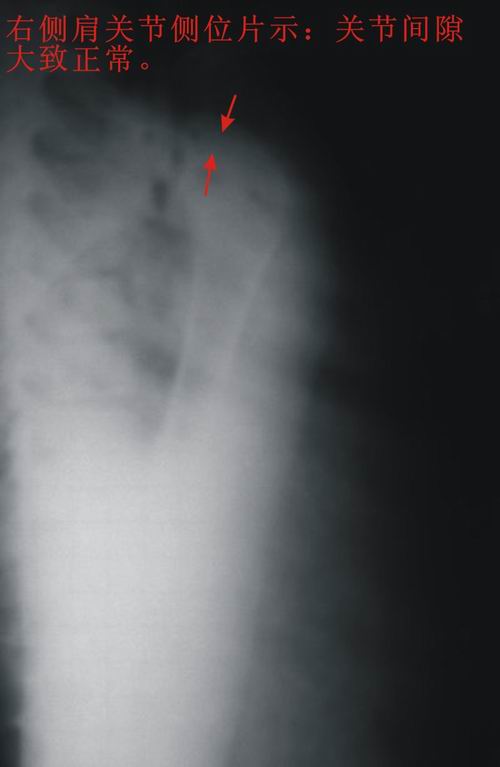

患者,男,13岁。自诉两月前双肩关节时有弹响,有时左、右肩关节轮换隐痛。但双上肢能抬举、左右旋转、屈伸自如。pe:双肩及双上肢皮肤无红、肿。触诊:双肩关节区域有抖动,似触心脏的搏动感,但抖动、搏动感能自控。双肩区域皮肤无发热。听诊:用耳贴近患者双肩区能听到弹响声。x线胸部后前位示:双肩关节间隙增宽,考虑双肩关节半脱位。双肩关节正侧位片示:双肩关节无明显脱位征象。双肩关节区域透视示:双肩关节解剖位时,双肩关节间隙增宽(与胸部后前位的双肩关节间隙相等),也能见双肱骨头在双肩关节腔内上、下移动约1cm左、右。但患者能自控(双肱骨头在双肩关节腔内不上、下移动)。请战友们详见患者相片、胸部后前位片、双肩关节正侧位片。我第一次碰到这样的病例(是否是神经性关节病“夏科氏关节”?),经验不足,希望能帮助诊断。亦请分析病因、病理机制,是什么原造成的?最好能提供治疗方法,谢谢!

双侧肩关节解剖位时,双肩关节间隙增宽,但肱骨头及周边骨质 关节腔均未见异常。与骨科专家会诊结果,目前只能诊断:肩关节松弛症!

双肩关节间隙增宽,但肱骨头及周边骨质 关节腔均未见异常。